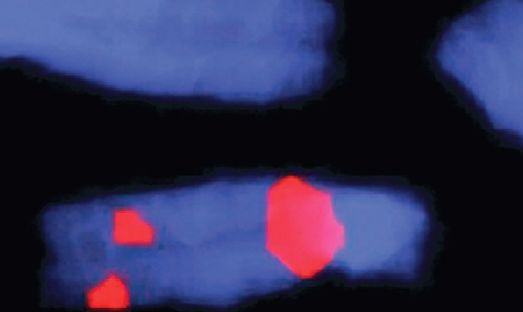

12 février 2025 - Soutenir les enfants atteints de la microdélétion 22q11. Perspectives de prise en charge par les familles et les professionnels de santé

Avec Sophie Ayoub, Université de Bâle, Colette Gendre, CHUV, Alessandra Strom, CHUV, modération par Ralf Jox, IHM